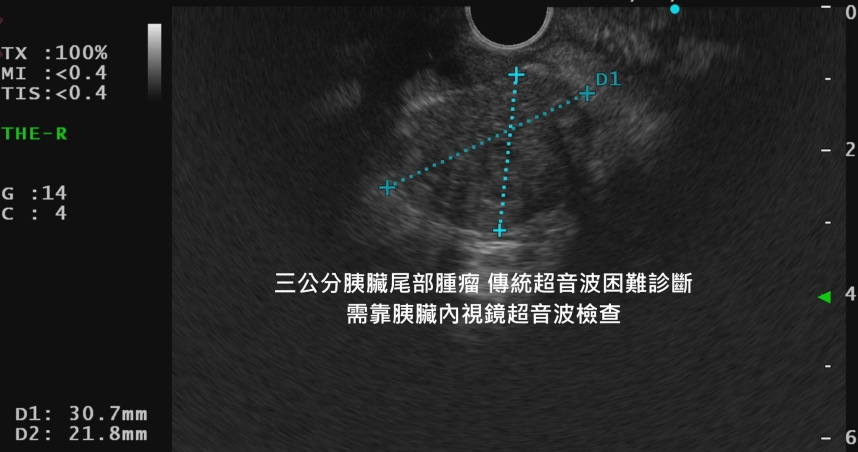

也由於家人認為情況不尋常,最後帶她前往林相宏門診。起初透過腹部超音波檢查,未見胰臟異狀。但林相宏醫師提醒,胰臟尾部腫瘤極易被忽略,因其位於胃腸氣體較多部位,傳統超音波不易穿透觀察。隨即安排進一步檢查,採用內視鏡超音波,短短3秒便發現典型胰臟癌腫瘤,腫瘤大小已超過3公分。